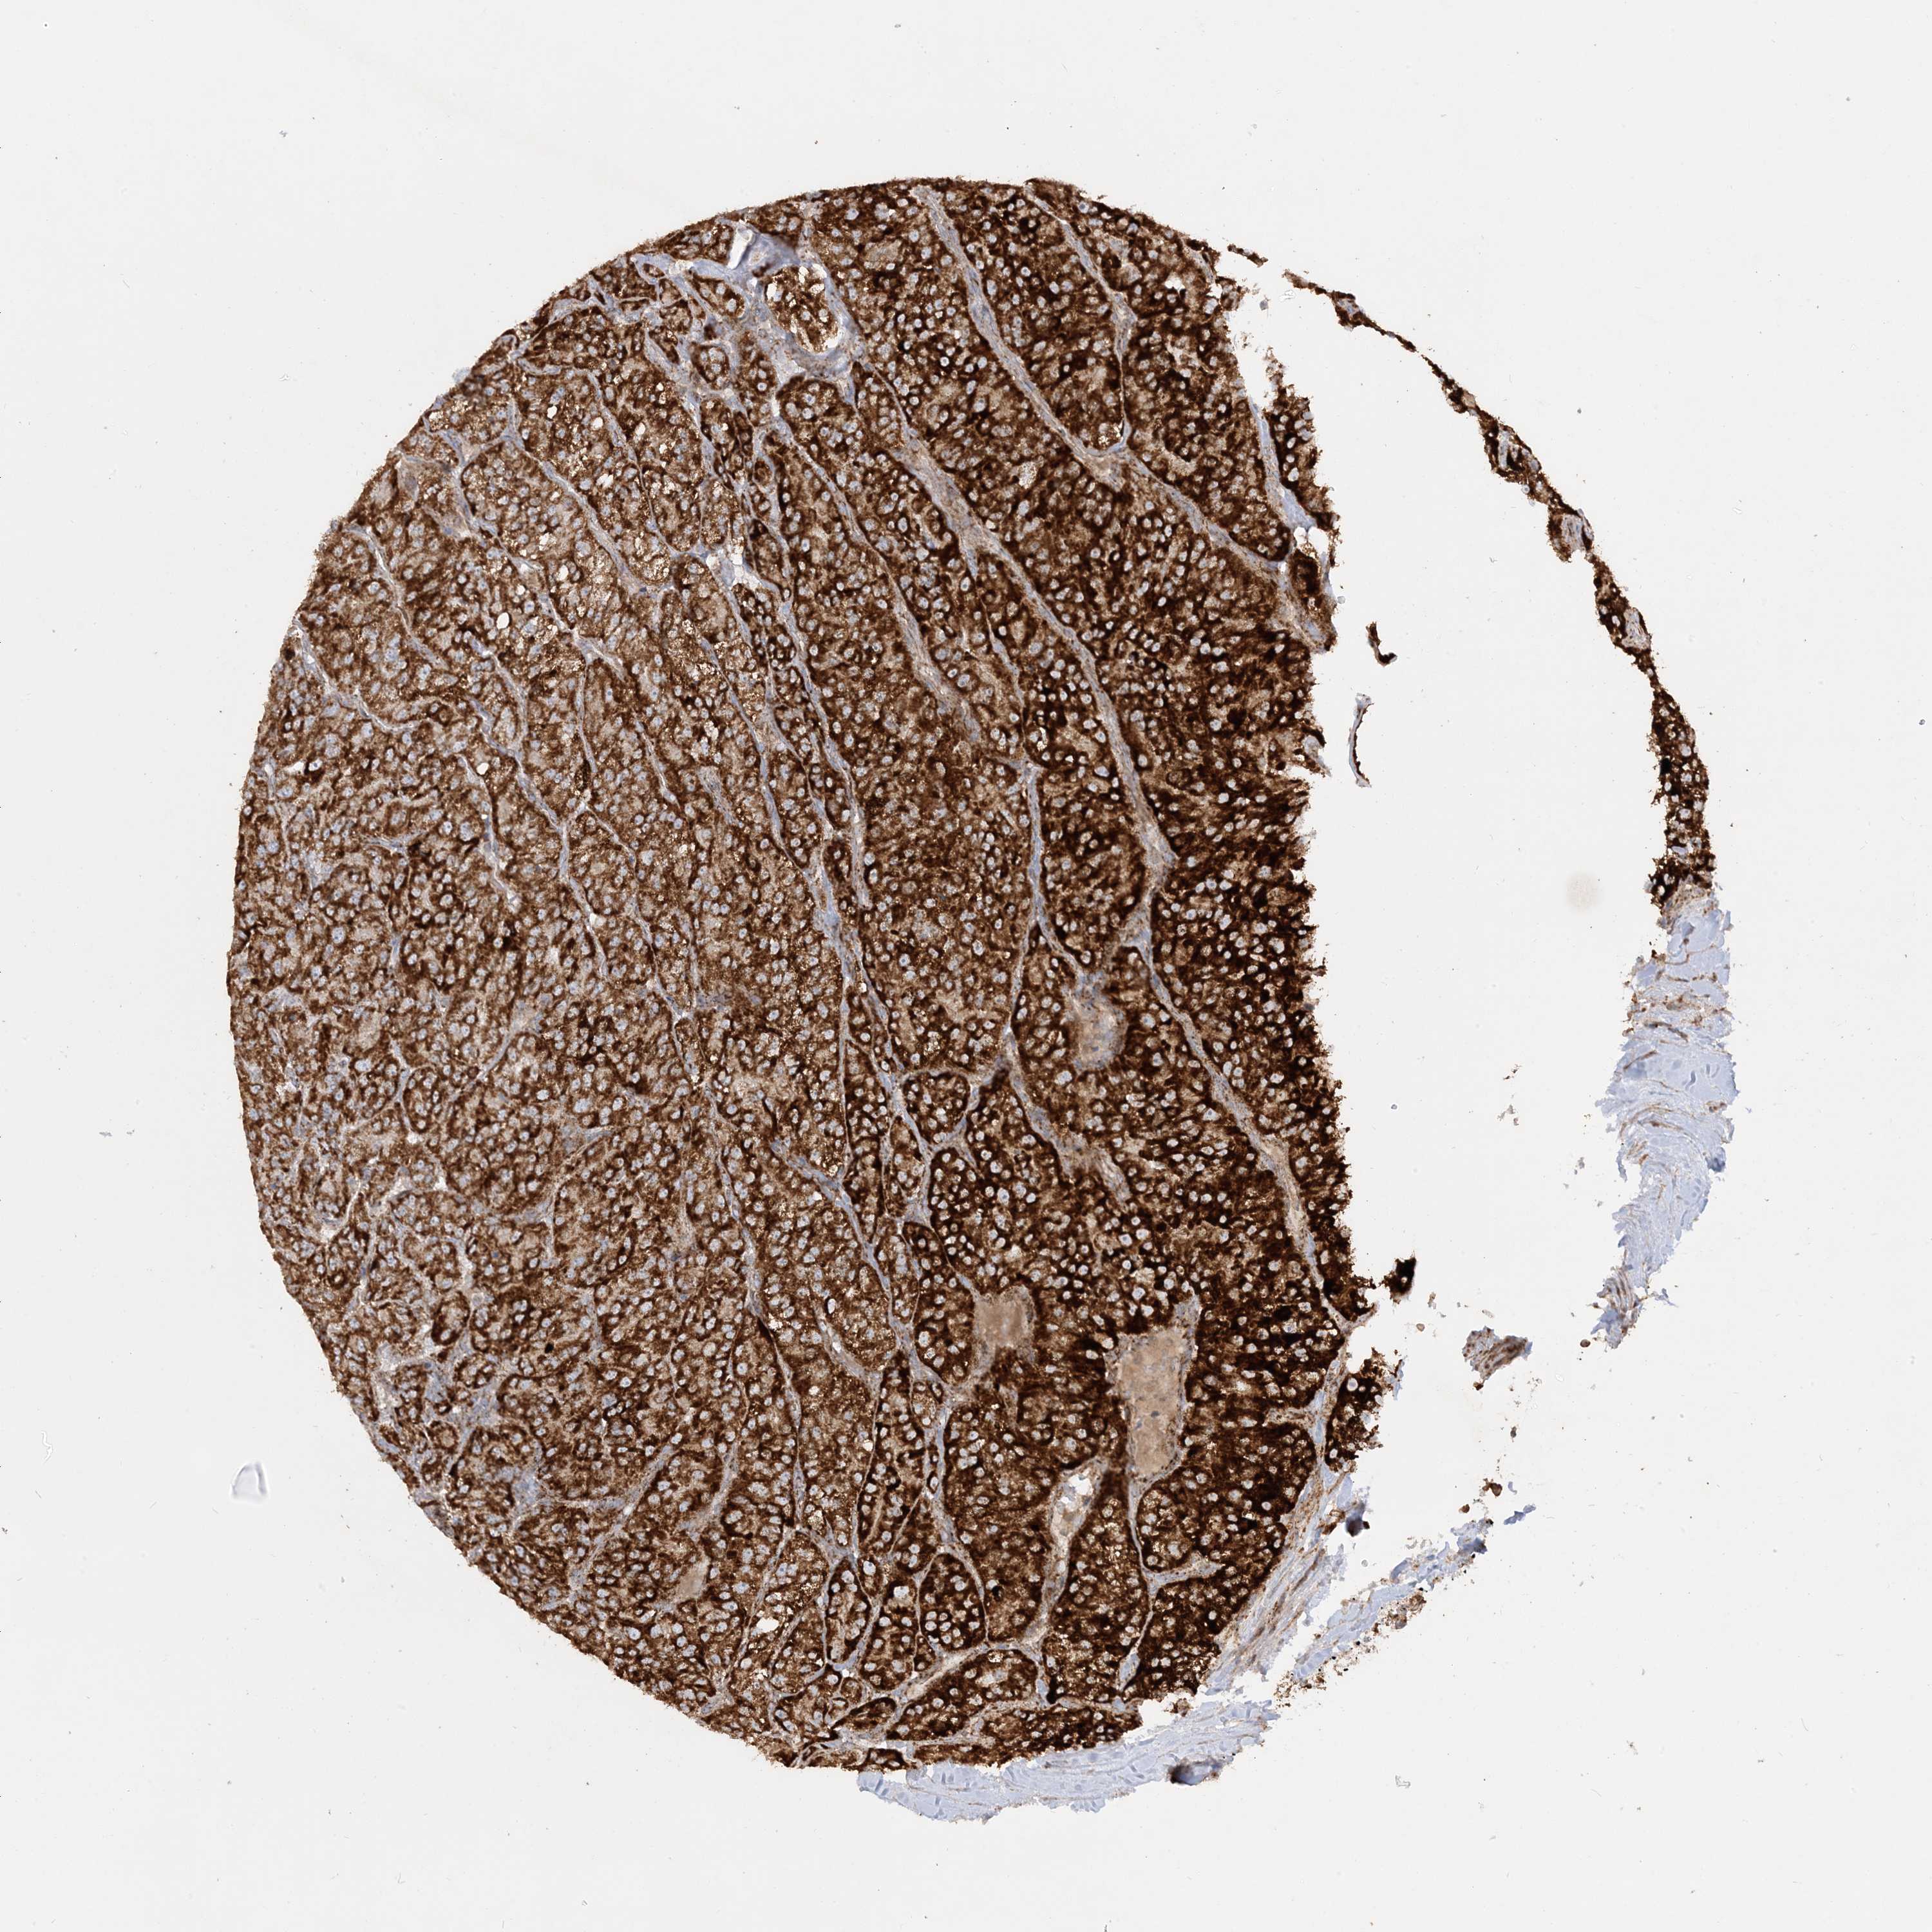

KIDNEY RENAL CLEAR CELL CARCINOMA (VALIDATION) - Interactive survival scatter ploti

The Survival Scatter plot shows the clinical status (i.e. dead or alive) for all individuals in the patient cohort, based on the same data that underlies the corresponding Kaplan-Meier plots. Patients that are alive at last time for follow-up are shown in blue and patients who have died during the study are shown in red.

The x-axis shows the expression levels (FPKM) of the investigated gene in the tumor tissue at the time of diagnosis. The y-axis shows the follow-up time after diagnosis (years). Both axes are complimented with kernel density curves demonstrating the data density over the axes. The top density plot shows the expression levels (FPKM) distribution among dead (red) and alive patients (blue). The right density plot shows the data density of the survived years of dead patients with high and low expression levels respectively, stratified using the cutoff indicated by the vertical dashed line through the Survival Scatter plot. This cutoff is automatically defined based on the FPKM cutoff that minimizes the p-score. The cutoff can be changed by dragging the vertical line or by entering a cutoff value in the square labeled "Current cut-off".

Under the Survival Scatter plot the p-score landscape (black curve; left axis) is shown together with dead median separation (red curve; right axis). Dead median separation is the difference in median mRNA expression between patients who have died with high and low expression, respectively. It is calculated as follows: median FPKM expression of dead patients with high expression - median FPKM expression of dead patients with low expression. This is intended to aid the user in visually exploring custom cutoffs and the associated p-scores and dead median separation.

Individual patient data is displayed and can be filtered by clicking on one or more of the category buttons on the top of the page. Categories describing expression level and patient information include: high, low, alive, dead, female, male and tumor stages. The scale of the x-axis can be toggled between linear and log-scale by clicking on the "x log" button. Mouse-over function shows TCGA ID, patient information and mRNA expression (FPKM) for each patient.

& Survival analysisi

Kaplan-Meier plots summarize results from analysis of correlation between mRNA expression level and patient survival. Patients were divided based on level of expression into one of the two groups "low" (under cut off) or "high" (over cut off). X-axis shows time for survival (years) and y-axis shows the probability of survival, where 1.0 corresponds to 100 percent.

NDUFAF3 is not prognostic in Kidney Renal Clear Cell Carcinoma (validation)

Best expression cut offi

Based on the FPKM value of each gene, patients were classified into two groups and association between prognosis (survival) and gene expression (FPKM) was examined. The best expression cut-off refers the FPKM value that yields maximal difference with regard to survival between the two groups at the lowest log-rank P-value. Best expression cut-off was selected based on survival analysis .

When clicking on this number, the vertical dashed line indicating cut-off, the interactive survival plot, and the Kaplan-Meier curve will be adjusted to show results based on the best expression cut-off.

: 67.62

TCGA RNA samplesi

RNA-seq data is reported as average FPKM (number Fragments Per Kilobase of exon per Million reads), generated by the The Cancer Genome Atlas (TCGA) .

Normal distribution across the dataset is visualized with box plots, shown as median and 25th and 75th percentiles. Points are displayed as outliers if they are above or below 1.5 times the interquartile range. FPKM values of the individual samples are presented next to the box plot.

Average pTPM 64.4

Number of samples 100